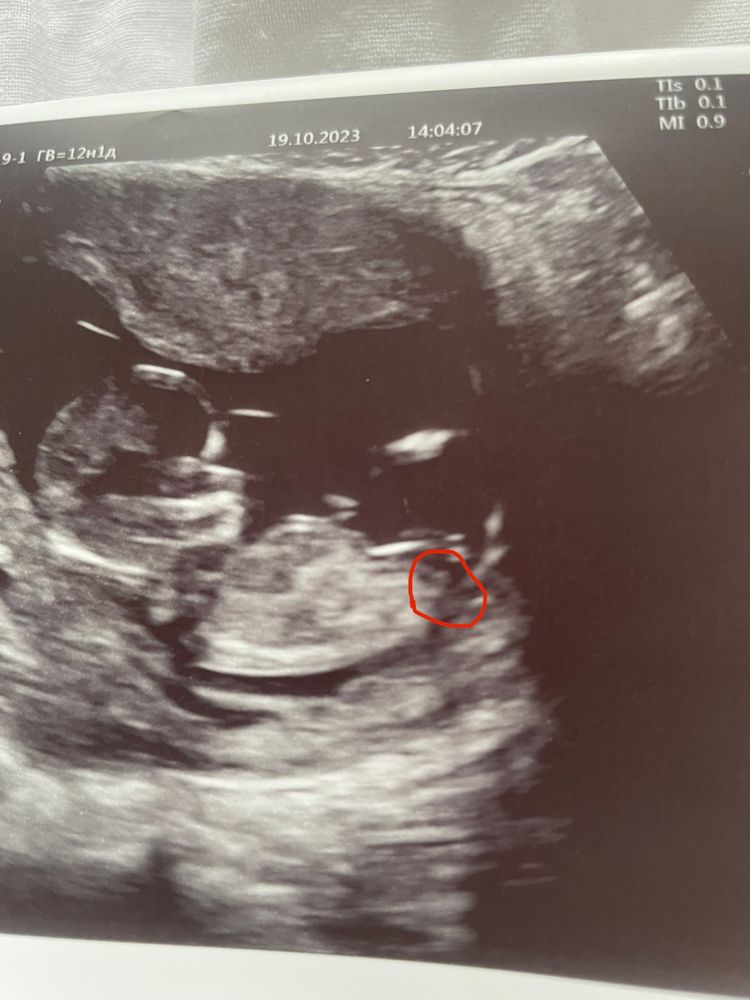

Катерина в Благополучная беременность 2 года Это половой бугорок? Или нет?) Пол малыша Посмотрите еще 20 записей на эту тему Лучший ответ Чашка утреннего кофе Если вас так волнует пол (а судя по количеству постов - волнует сильно) почему бы вам не сдать кровь на опредение пола и не мучиться? 21.10.2023 Ответить Отменить Ответить Таня Ну я б сказала, что да и это мальчик. Но лялька вполоборота лежит и тут это может быть часть ноги, руки, пуповины и тд) 21.10.2023 Ответить Наталья на таком малом сроке можно только гадать-)) Или потерпите до второго скриннинга, или да, сдавайте на определение У хромосомы-) 21.10.2023 Ответить Ксения Сдайте уже кровь на определение пола. 21.10.2023 Ответить Закрашиваю кружочек ❤️ Закрашиваю кружочек🩵 Чаты Беременных Выберите чат: Январята-2026 Февралята-2026 Мартята-2026 Апрелята-2026 Майчата-2026 Июнята-2026 Июлята-2026 Августята-2026